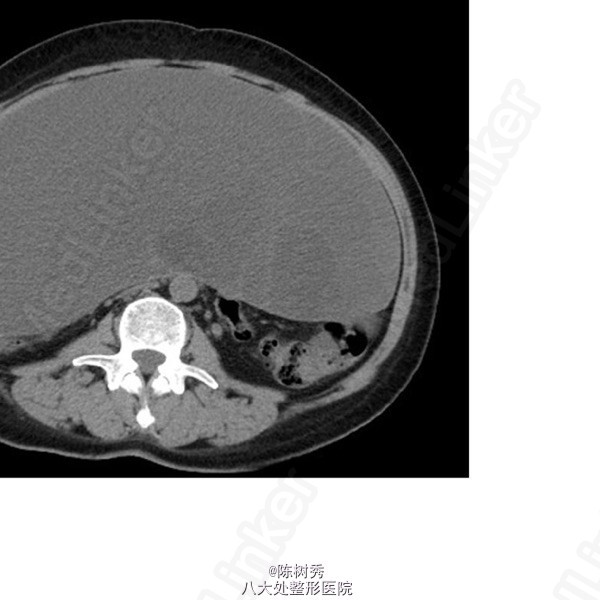

主 诉:发现腹部肿物1月 现病史:患者1月前体检发现腹部巨大肿物,无伴腹胀、腹痛、腹泻、便秘等不适,当地医院超声检查提示腹盆腔巨大肿物,性质不明,建议至上级医院就诊。为求进一步诊治,来我院就诊。我院2015-05-07腹盆增强CT+小肠重建:腹盆腔内巨大多房囊性肿块;盆腔少量积液;子宫节育器置入后改变。门诊拟“腹部占位”收入我科。 自起病以来,精神、睡眠、食欲可,大小便如常,体重下降5KG。

全身浅表淋巴结未及。腹部膨隆,未见胃肠型及蠕动波。腹软,全腹无压痛、反跳痛,全腹可及巨大肿物,质韧,边界清晰,活动度差,大小约30x27x12cm,无压痛及反跳痛。肝、脾肋下未及肿大,Murphy’s征(-),肝区叩痛(-),肾区无叩痛,肠鸣音可,移动性浊音(-)。直肠指诊(胸膝位):肛周皮肤无异常;进指7cm未及明显肿物,退指指套无血染。 辅 助 检 查 2015-05-07 腹盆增强CT+小肠重建 腹盆腔内巨大多房囊性肿块,请结合临床;盆腔少量积液;子宫节育器置入后改变。 2015-05-07 胸部CT平扫 双肺散在淡片、磨玻璃密度影;左肺门及纵隔多发小淋巴结,部分钙化;双侧胸膜局部增厚;心包稍厚。